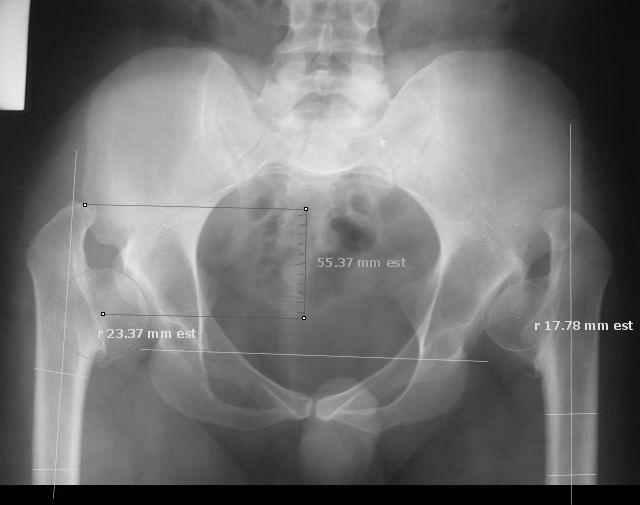

Re: Congenital coxa vara

I took the liberty of 'marking up' your image with software tools we have been developing. Please note the measurements in millimeters are 'unscalled' because the image is not calibrated.

Derek Cooke